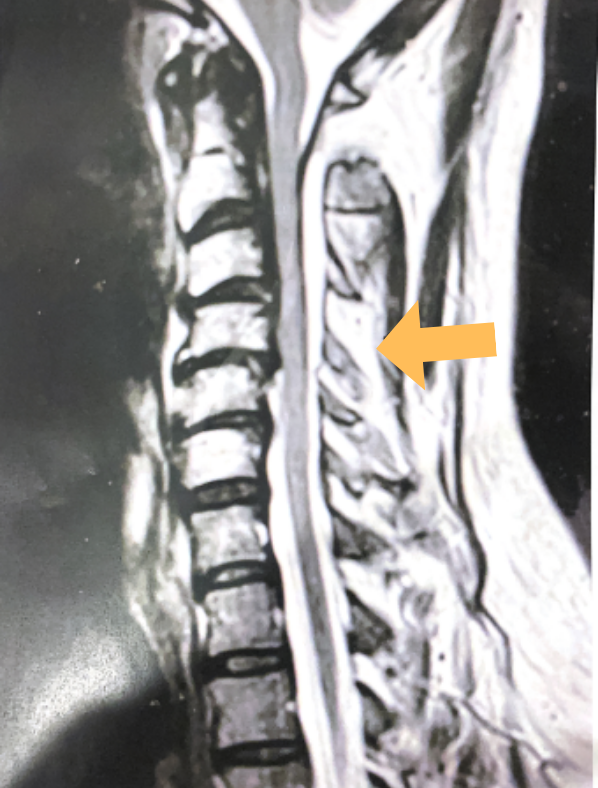

Back:

Revision Surgery Treats Intractable Neck Pain & Cervical Deformity

Author: Benjamin R. Cohen M.D., F.A.A.N.S., F.A.C.S., Read More!